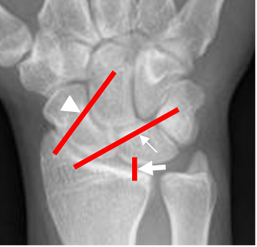

Fig 2. Ligamentos extrínsecos anteriores.

Rx AP. Ligamentos radioescafogrande (Punta de flecha), radiolunopiramidal

(Flecha delgada) y radiolunado (Flecha gruesa).